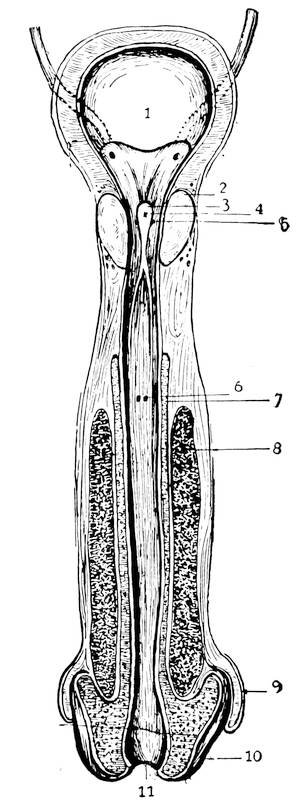

The male genitals, scrotum, testicles, descent of testicles, vas deferens, spermatic cord, seminal vesicles, ductus ejaculatorii, urethra, prostate, colliculus, sinus pocularis, penis.

In the male the genital tubercle increases enormously in size to form the penis. Its extremity becomes bulbously enlarged and forms the glans penis. The lips of the groove or rather of the vestibule, since by this time the urogenital membrane had broken through and had transformed the sinus urogenitalis into the vestibule, the so-called genital folds, meet together and fuse, thus converting the vestibule and the groove into the terminal portion of the male urethra and bringing it about, that the ductus ejaculatorii and the sinus pocularis open upon the floor of that passage. The prostate, consisting of several independent glands, has also its openings at this point. In its development the prostate belongs to the urethra as well as to the sinus urogenitalis. The two genital swellings are brought closer together in the male and form the scrotum, a sac containing two separate pouches into which the testes descend.

Scrotum.—The main generative glands in the male, the testicles, are situated within a bag, the so-called scrotum, outside of the abdominal cavity. This bag or pouch, hanging between the thighs, below the symphysis, consists of two compartments which are separated by the septum scroti. The scrotum may be considered as a diverticle of the anterior abdominal wall. Before the descent of the testicles from the abdominal cavity, two diverticles of the abdominal wall are formed, at two points anteriorly to the genital swelling, where later on the inguinal canals are found. The diverticles extend to the swelling and coalesce to form the bag. The raphe, or last, at the point of their union, can be observed through the entire life of the individual. This median raphe runs from the perineum to the penis, indicating the inner division of the scrotum.

The scrotum being a derivative of the abdominal wall, it follows that its wall will consist of the same elements as the abdominal wall. The first layer of the abdominal wall, the epi30dermis or cutis, forms also the epidermis of the scrotum. The fascia superficialis abdominis constitutes the second layer of the scrotum, or the tunica dartos. The musculus obliquus abdominis externus goes to make up the third layer, the so-called Cooper’s fascia. The musculus obliquus abdominis internus forms the fourth layer, or the musculus cremaster externus. The musculus transversalis abdominis furnishes the cremaster internus muscle, and the tunica vaginalis communis, or the fifth layer. Finally, the double layer of the abdominal peritoneum forms the tunica vaginalis propria of the scrotum. Between the two lamina of this tunica is found some fluid which, when pathologically increased, constitutes the anomaly called hydrocele.

Urethra.—The urethra is divided into three parts, the pros34tatic, the membranous and the cavernous parts. The prostatic part is the widest portion of the entire urethra. It is surrounded by an unstriped muscular layer and the muscles of the prostate. The membranous part is the narrowest, shortest, and most thin-walled portion of the three parts of the urethra. It is entirely surrounded by the muscular fibres of the diaphragma urogenitale, which takes here a circulatory course. It is in this way situated35 on the border-line of the abdominal cavity and the exterior, within the abdominal wall. The cavernous portion of the urethra is surrounded by the corpus cavernosum urethrae. This portion shows two dilatations, one in the bulbous part, just anterior to the termination of the membranous part, where the ducts of the two Cowper’s glands open; the other dilatation is near the end, behind the meatus, forming the so-called fossa navicularis. The meatus itself is the narrowest part of the entire urethra. Numerous mucous crypts, the glands of Littré and certain lacunae, the largest among them near the fossa, open into the lumen of this part of the urethra. The entire urethra is lined with a cylindrical epithelium, except at the fossa navicularis. The latter is covered by a layer of pavement epithelia. The length of the urethra is about 18 centimeters. In the usual state the urethra possesses only a virtual lumen, i. e., the walls touch each other.